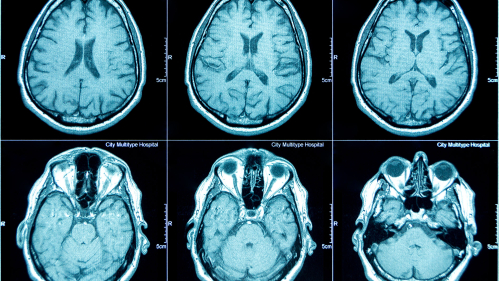

New Method Makes Brain Imaging Research More Accessible for Psychiatric Studies

A new approach to analyzing brain scans could help researchers better understand psychiatric illness using much smaller groups of patients than previously thought necessary, potentially accelerating the development of more precise mental health treatments.

The research identified specific brain networks involved in cognitive function. They also observed decreased connectivity between these regions and areas handling basic sensory information. This pattern was consistent across different psychiatric conditions, suggesting shared biological mechanisms may underlie cognitive problems in various mental illnesses.